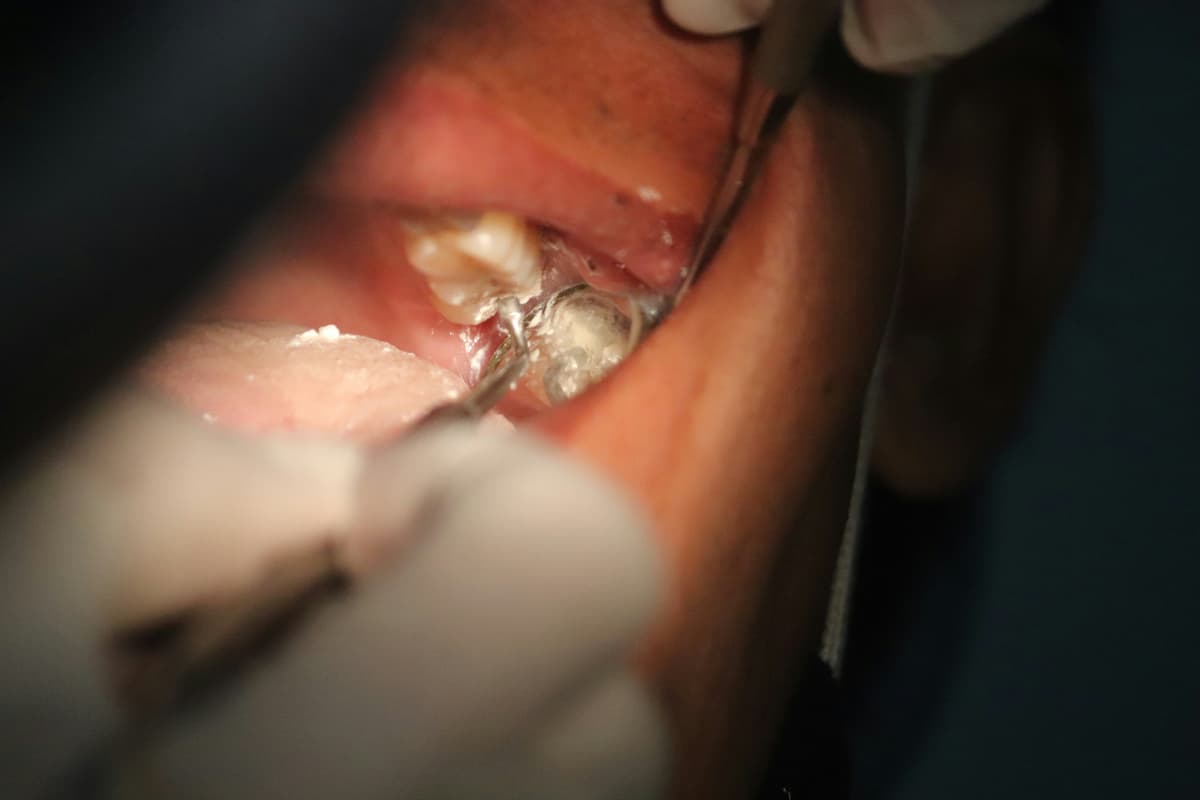

At our dental clinic, we understand how dental pain, infection, or damaged teeth can affect your comfort and confidence. That is why we offer professional dental extraction to safely remove problematic teeth and restore your oral health. Dental extraction may be recommended for severely decayed, broken, impacted, or painful teeth that can no longer be saved.

Your dental extraction journey begins with a thorough dental examination and digital X-rays so we can clearly understand your condition and plan the safest treatment. Our dental clinic uses modern techniques and effective anesthesia to ensure a gentle and comfortable extraction experience for both children and adults.